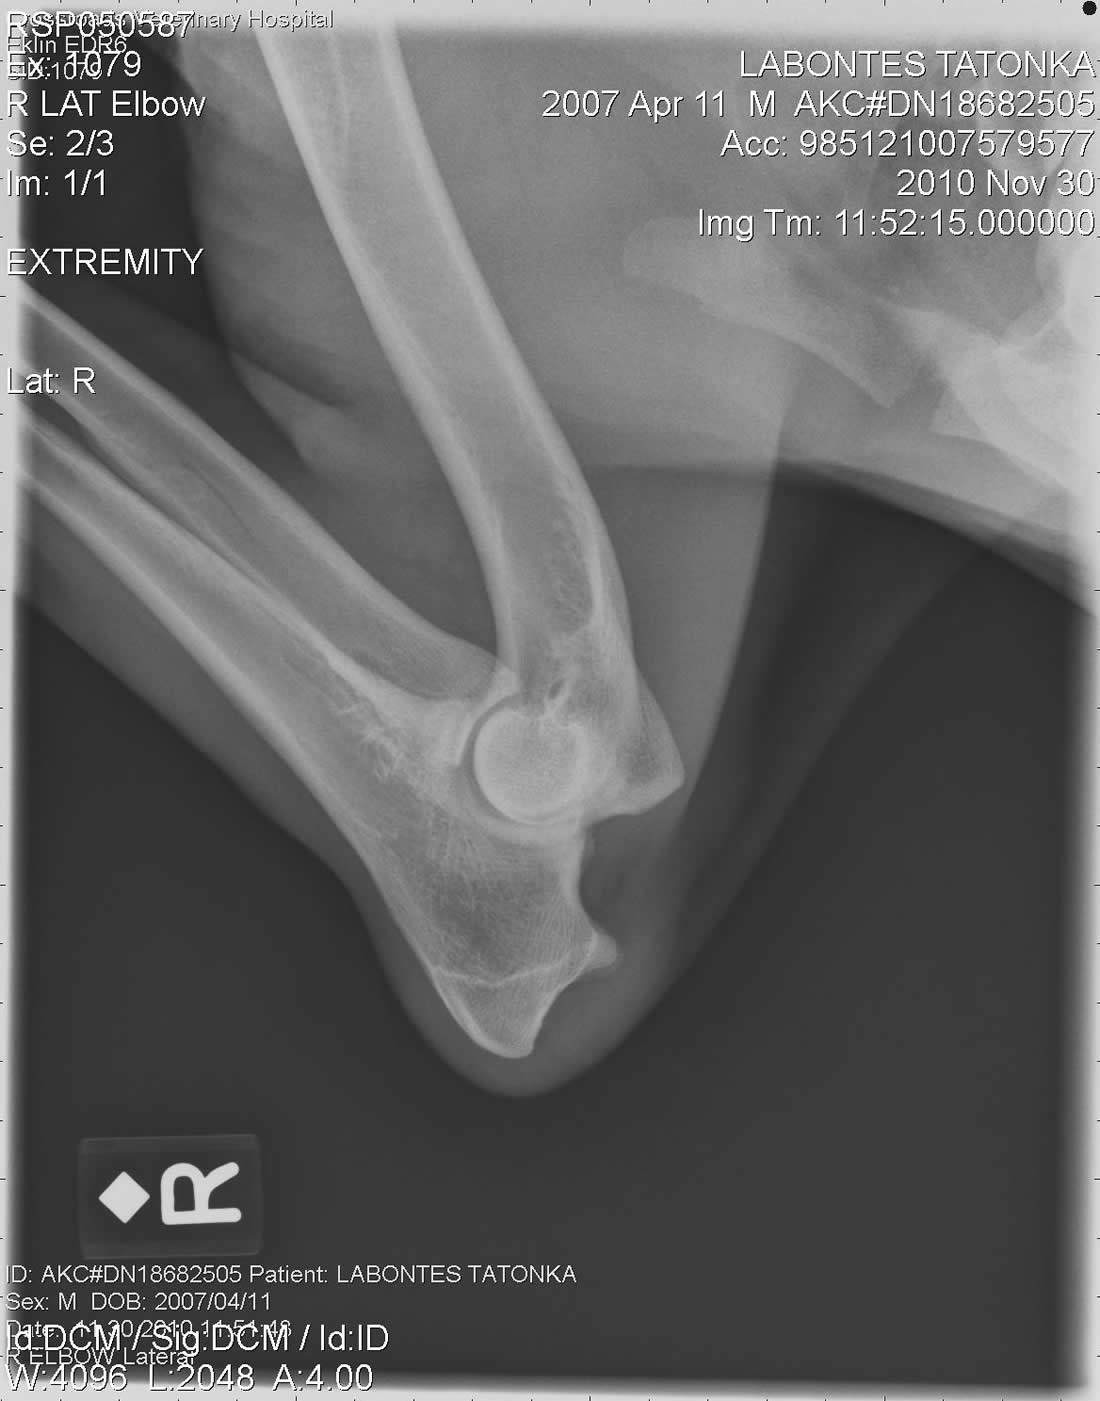

Right Elbow X-Ray